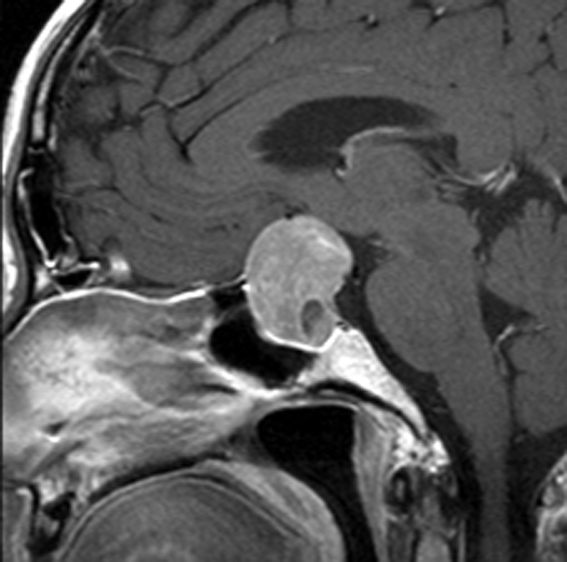

典型的なMRIの画像です

下垂体腺腫のMRIです。両側の視野障害(両耳側半盲)のために手術を受けた患者さんのものです。この腫瘍は非機能性腺腫といってホルモンを出さない腫瘍でした。少し大きめでしたが全部取れて視野の障害はよくなりました。

左の2枚はガドリニウム造影剤を使って写したもので腫瘍の形がよくわかります。右の1枚はT2強調画像と言います。MRIでは撮影の仕方によって見え方が違います。